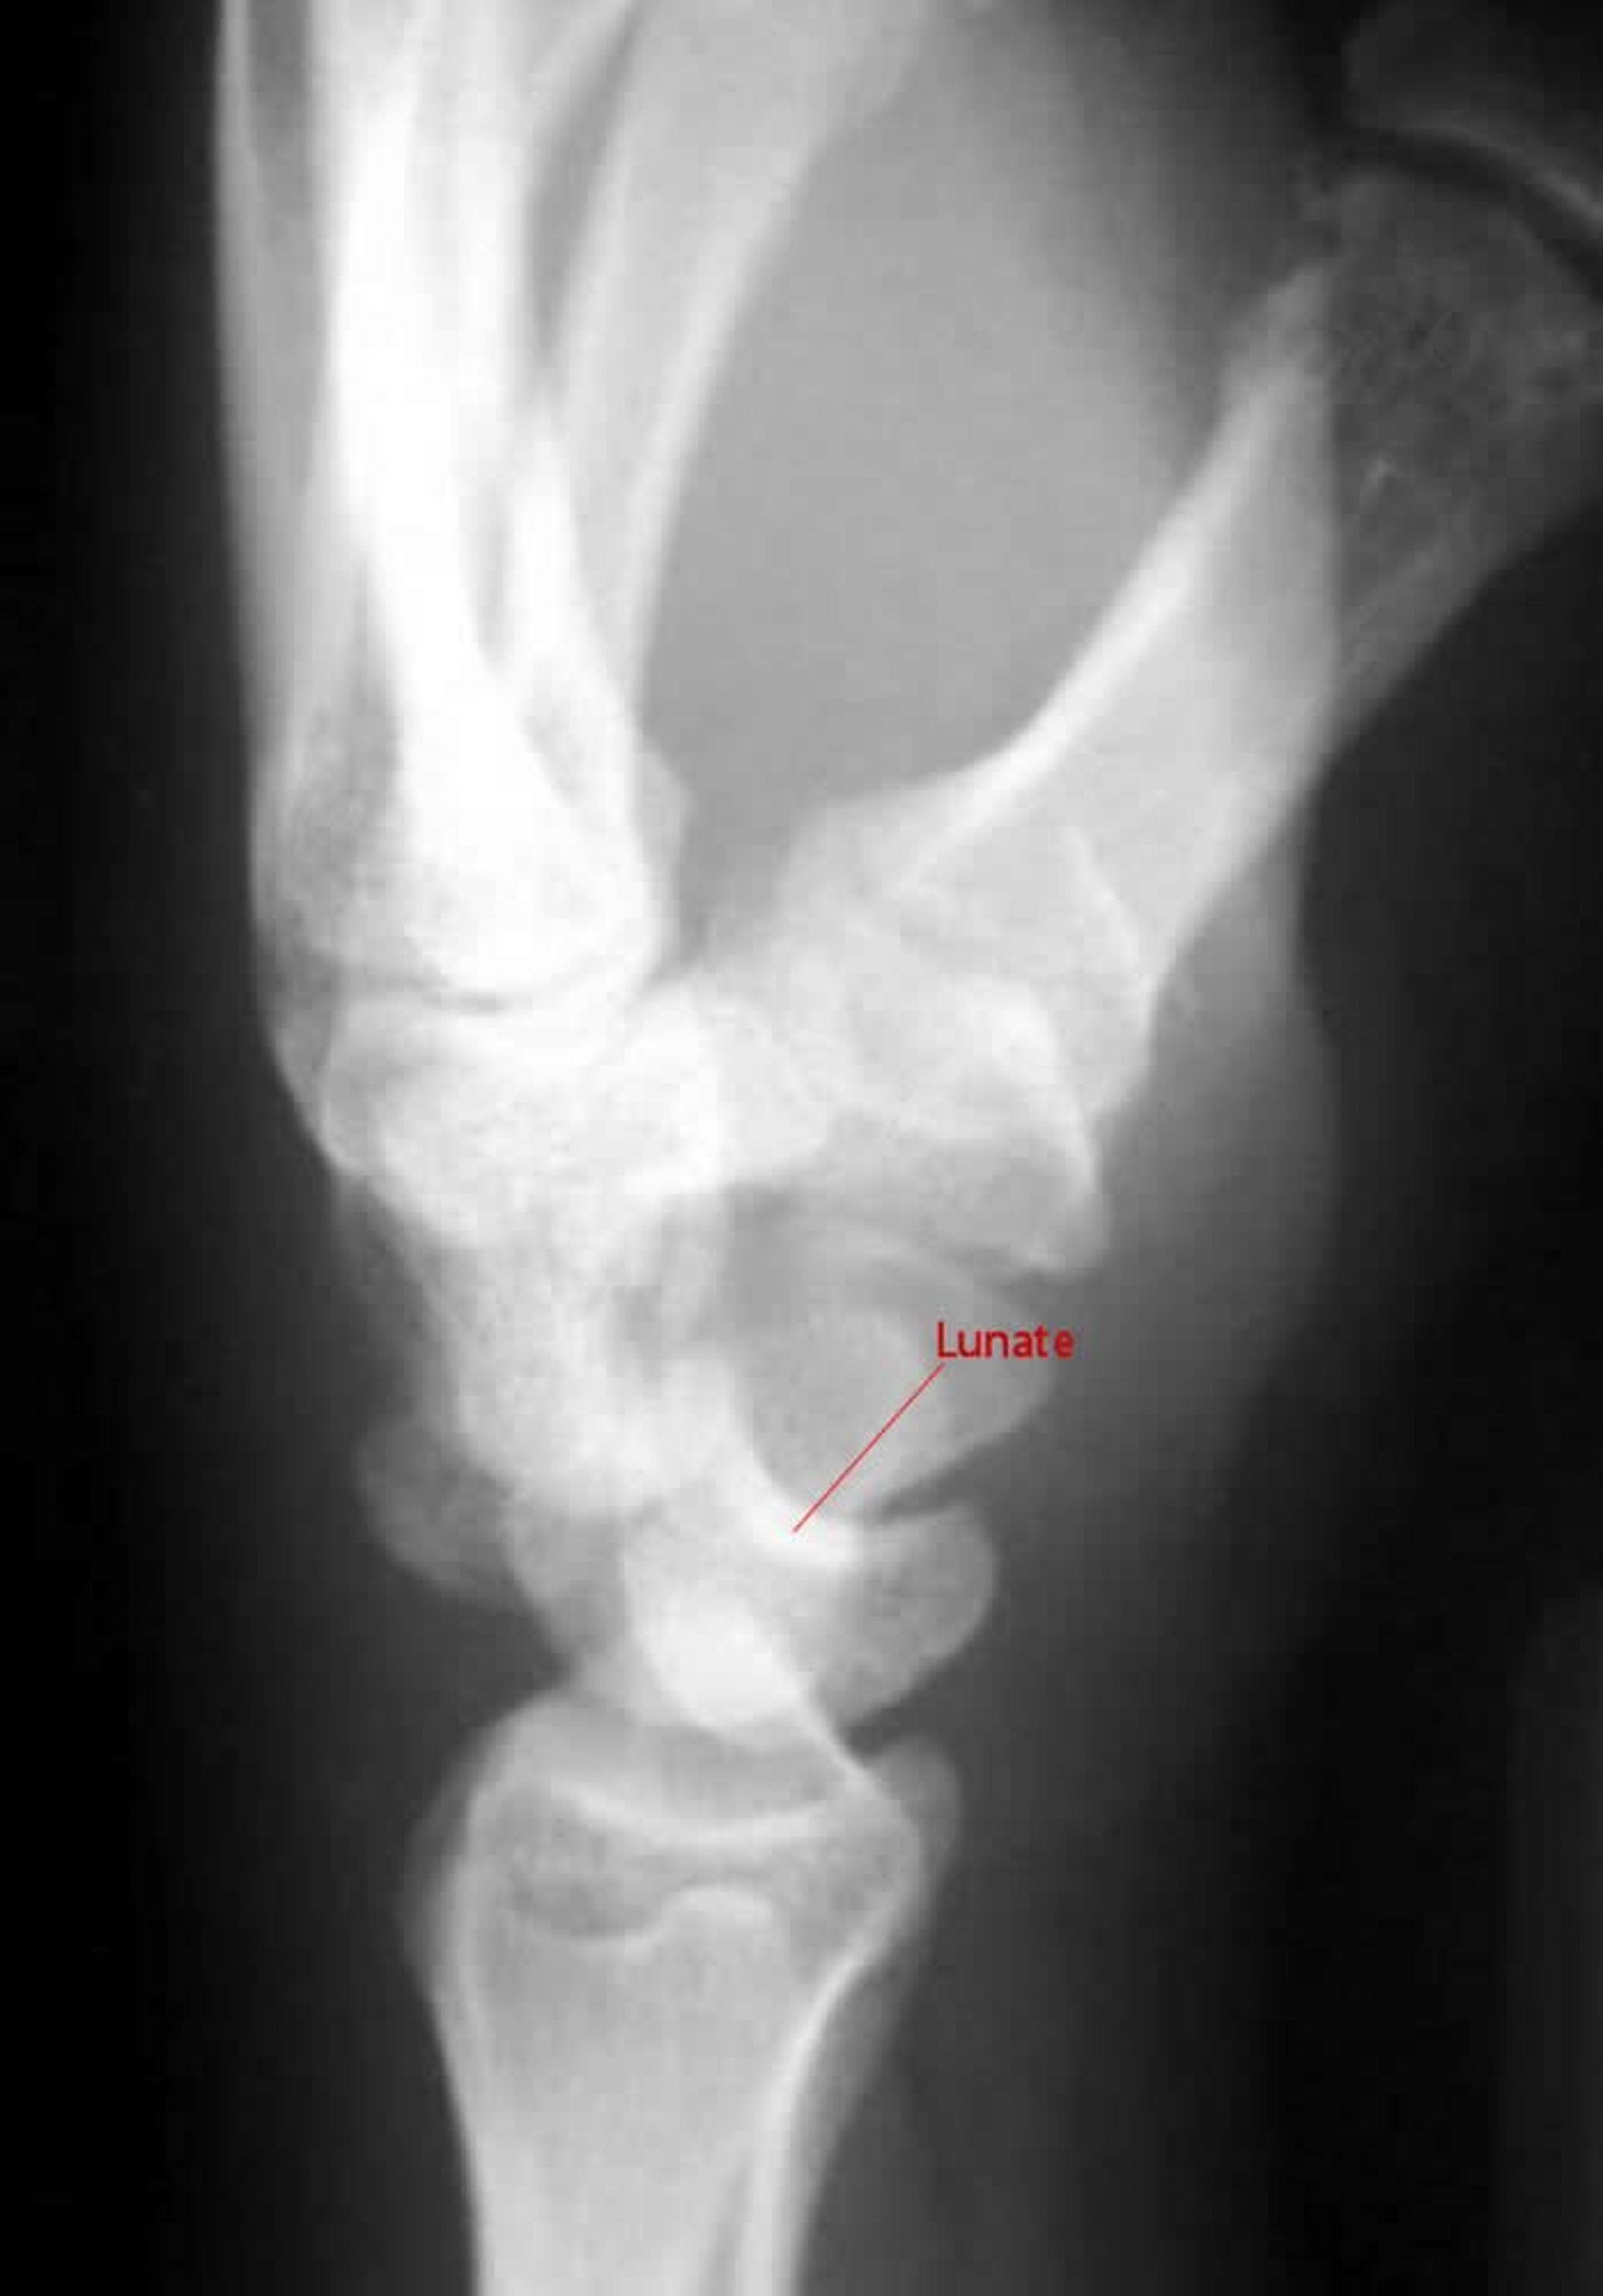

Перилунарный вывих кисти

На боковой части снимка рентгенограммы при перилунарном вывихе кисти головчатая кость не формирует сустав с полулунной костью.

Image courtesy of Danielle Campagne, MD.